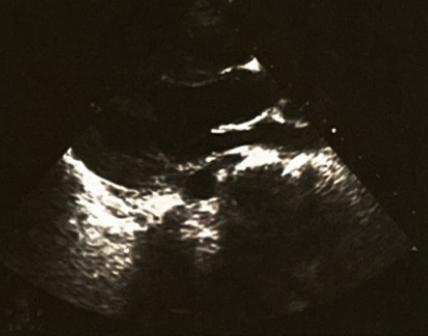

◇入院第7天:超声心动图提示各房室内径正常,LVEF 60%(图4),入院第8天撤除ECMO,最终病情稳定出院。

图4、病情恢复后超声心动图